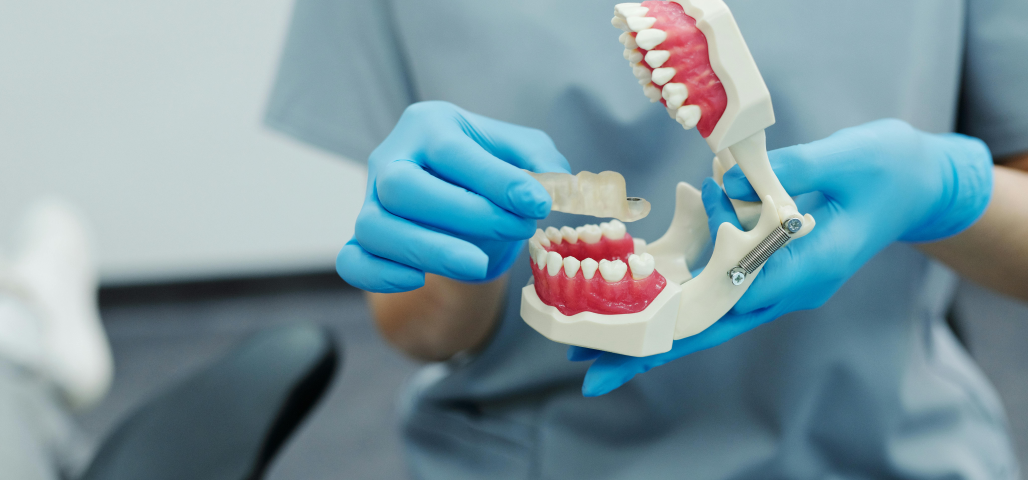

Chirurgie orale

La chirurgie orale regroupe un ensemble d’interventions réalisées au niveau de la bouche, des dents et des mâchoires, allant de l’extraction des dents de sagesse aux actes plus complexes comme les kystes, les freinectomies ou les préparations implantaires.

Au cabinet du Dr Duroux à Cannes, ces actes chirurgicaux sont pratiqués avec rigueur et précision, dans un environnement sécurisé et adapté. L’objectif est d’assurer une prise en charge efficace, en limitant l’inconfort du patient et en favorisant une cicatrisation rapide.